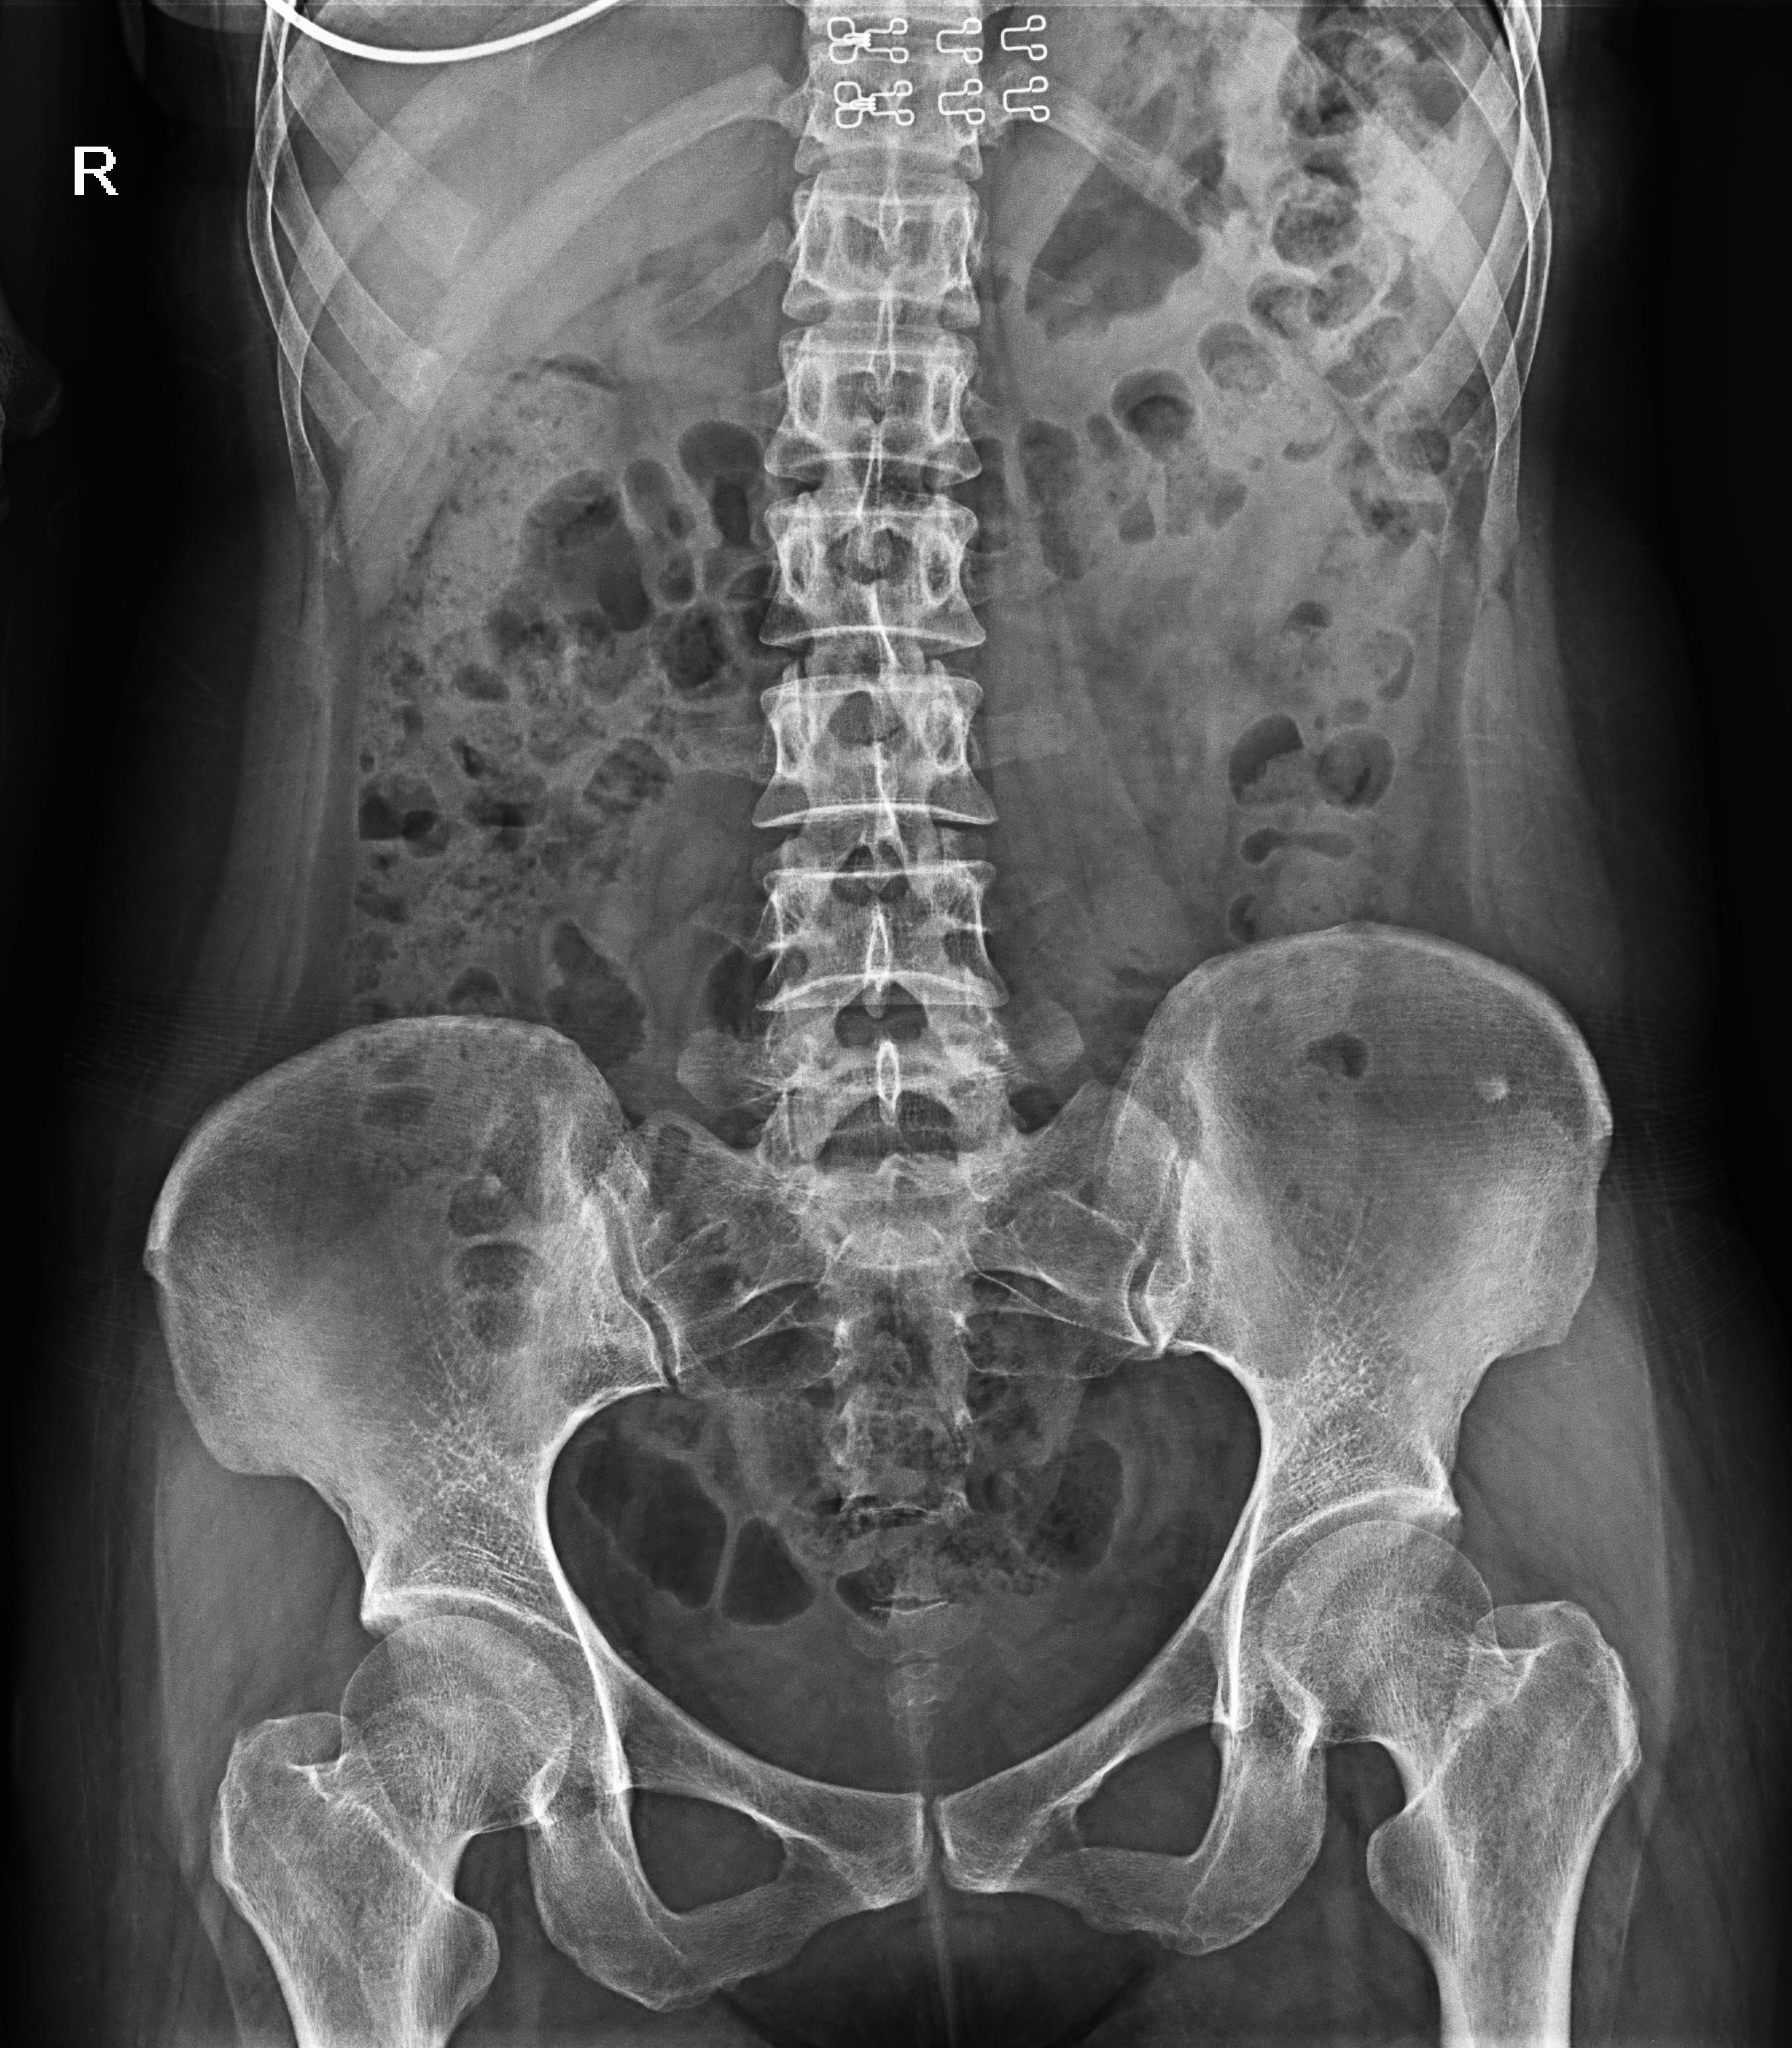

盆骨 (2)